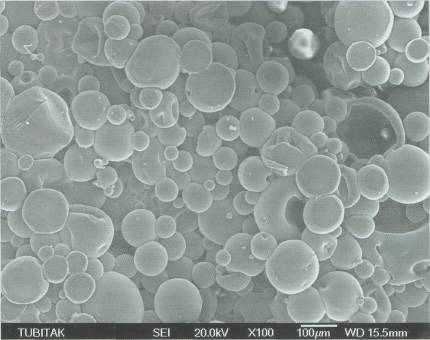

adamları orijinal karaciğer benzeri bir model oluşturdular. Yapay karaciğer yaratmada en önemli basamak, karmaşık damar yapısını oluşturmak. Bu nedenle ilk olarak, vücuttan çıkartılmış bir karaciğerin damarlarının içine, özel bir sıvı plastik materyal enjekte ediliyor. Bu sıvı kısa süre içinde katılaşarak damarların şeklini alıyor. Daha sonra karaciğer dokusu özel sıvılarla eritilerek yok ediliyor. Geriye yalnızca katılaşmış ve damar şeklini almış olan madde kalıyor. Kurumuş ağaç dallarına benzeyen bu yapı, karaciğerin damar yapısını temsil ediyor. Bu yapının görüntüleri bilgisayara aktarılarak üç boyutlu görüntüler elde ediliyor. Bu görüntüler yardımıyla silikon kalıplar hazırlanıyor. Silikon kalıpların içine polilaktik glikolik asit (PLGA) yapısındaki bir madde dökülüyor. Böylece karaciğer

damarlarının organik bir iskeleti oluşturuluyor. Bu iskeleti oluşturduktan sonraki aşamaysa hücrelerin oluşturulması. Damar iskeleti çevresine yerleştirilen karaciğer hücreleri, belirli büyüme faktörleri yardımıyla çoğalarak organın kalın etli kısmını oluşturuyorlar. Bir sonraki aşamaysa damarın oluşturulması. Bunun için süngerimsi yapıda olan PLGA içine damar hücreleri enjekte ediliyor. İskelet, hücrelerin çoğalması için gerekli büyüme faktörlerini ve besin maddelerini içeriyor. Damar hücreleri iskelet boyunca ilerleyerek karaciğer hücrelerine yapışıyor. Burada çoğalan damar hücreleri, iskelet çevresinde birleşerek tam bir damar yapısı oluşturuyorlar. PLGA iskelet birkaç ay içinde kendiliğinden eriyerek geride karaciğer hücreleri ve içinde damarları olan yapay bir organ bırakıyor. Bu şekilde oluşturulan yapay karaciğer hayvanlarda denendi. Oldukça iyi kan akımının sağlandığı bu organlarda dışarı kan sızıntısı da gözlenmedi.

Tabii bu teknolojiyi ideal şekle getirmek çok kolay değil. Karaciğer içinde değişik görevleri olan milyonlarca hücre var. Yalnızca bir gram karaciğer dokusunda yaklaşık 100 milyon karaciğer hücresi bulunuyor. Hücrelerin gerekli noktalara yerleştirilmesi ve buradaki konumlarını korumalarının sağlanması oldukça güç. Yapay karaciğer oluşturulmasında karşılaşılan diğer bir güçlükse, organın mikroplardan arındırılması. Yapay organların içine hiçbir mikrobun girmemesi gerekiyor. Bu nedenle, çalışmalarda kullanılan tüm cihaz ve aletlerin steril, yani mikroptan arındırılmış olmaları çok önemli.